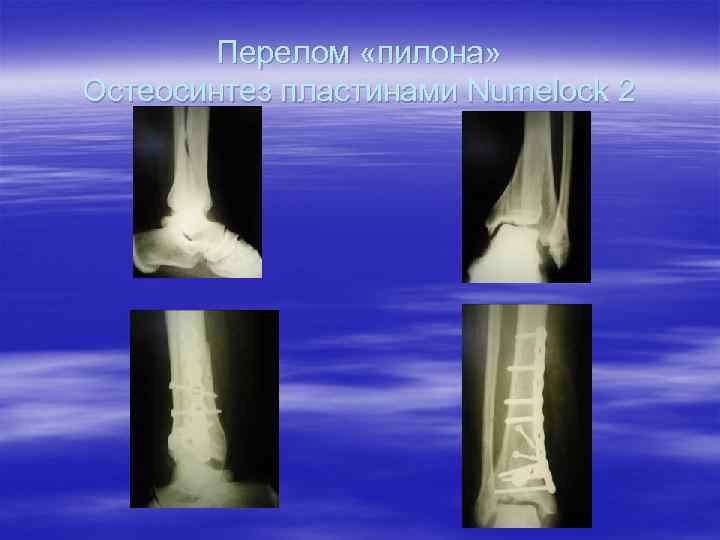

Перелом «пилона» Остеосинтез пластинами Numelock 2